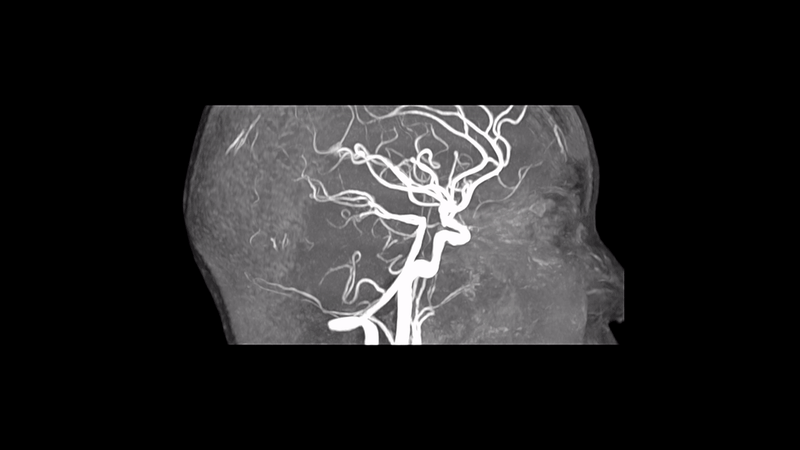

갑작스럽고 강도가 큰 경고성 두통은 뇌혈관 병변 가능성이 있어 정밀한 영상분석이 필요합니다. 본 증례는 뇌 MRA에서 3mm 뇌혈관 돌기가 확인되어 상급병원으로 신속 전원했습니다.

MRA에서 우측 뇌혈관 3mm 혈관 돌기 확인 → 상급병원 전원 및 치료 계획 수립.

• MRA: 혈관 돌기 MRA: 혈관 돌기

• 3mm 뇌혈관 돌기 3mm 뇌혈관 돌기